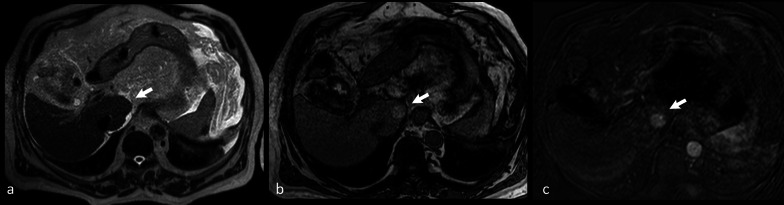

Cirrhotic nodules, including regenerative nodules, dysplastic nodules and HCC can appear hyperintense on unenhanced T1-w. imaging [55–57] (Fig. 7).

Fig. 7.

Axial turbo spin echo (TSE) T2-w. image a of the abdomen does not show any focal lesion on the caudate lobe of the liver (arrow). On nonenhanced opposed-phase gradient echo (GE) T1-w. image b a well-defined hyperintense nodule (arrow) at the same level can be identified. Contrast-enhanced fat-saturated GE T1-w. scan in the arterial phase (obtained after subtraction of signal of nonenhanced image) (c) shows distinct contrast-enhancement of the lesion (arrow). Final diagnosis was low-grade hepatocellular carcinoma

According to Chou et al., in cirrhotic liver 44% of T1-w. hyperintense nodules were dysplastic nodules, and the remaining 56% were nodules of HCC [58]. Thus, the mere hyperintensity on T1-w. images does not allow a differential diagnosis between benign and malignant hepatic nodules. Focal hepatic lesions showing hyperintensity on unenhanced T1-w. imaging might be due to lesions containing T1-shortening elements (e.g., glycogen, fat, copper, highly concentrated proteins) [58, 59]. Namely, concentration of paramagnetic Cu2+ ions has been demonstrated in hyperintense hepatic nodules [60].